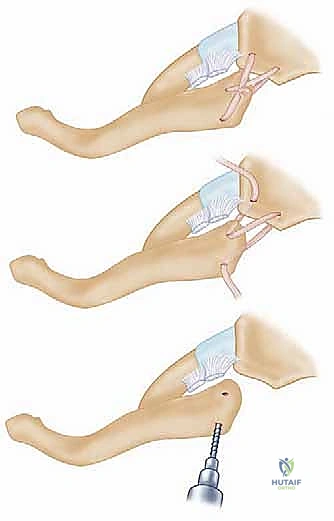

Once the joint is exposed, the pathology is assessed. In an acute setting, the torn remnants of the anterior and posterior capsule are identified and tagged with heavy non-absorbable sutures. If the intra-articular disc is irreparably torn or blocking reduction, it may be excised, though preserving it is preferable if possible. Reduction of the joint is then performed under direct visualization. For a posterior dislocation, a bone hook or a robust towel clip is placed around the medial clavicle to pull it anteriorly and laterally, while an assistant applies lateral traction to the abducted arm.

SURGICAL WARNING: The Absolute Contraindication of Pin Fixation

It is an absolute, non-negotiable tenet of orthopedic surgery that smooth or threaded Kirschner wires, Steinmann pins, or any form of unconstrained wire fixation must never be used to stabilize the sternoclavicular joint. The dynamic forces of the shoulder girdle, combined with respiratory excursion, inevitably lead to hardware migration. Pins migrating posteriorly have caused fatal cardiac tamponade, aortic laceration, and tracheal perforation. The literature is replete with catastrophic, lethal complications from this historically flawed technique. Pin fixation of the SC joint is considered below the standard of care.

Modern stabilization relies on robust biological reconstruction. While primary repair of the capsule using suture anchors in the manubrium can augment the construct, a figure-of-eight graft reconstruction is the gold standard for restoring multiplanar stability. A semitendinosus or gracilis autograft (or allograft to minimize donor site morbidity) is preferred due to its length and tensile strength.

Drill holes, typically 4.0mm to 4.5mm in diameter, are meticulously created. In the medial clavicle, two holes are drilled from anterior to posterior, approximately 1 cm lateral to the articular margin and 1 cm apart. In the manubrium, two corresponding holes are drilled. Critical Step: When drilling the manubrium and the clavicle, a malleable retractor or a broad periosteal elevator must be placed deep to the bone to protect the mediastinal structures from the drill bit plunging. The drill must always be directed from anterior to posterior, with precise control.